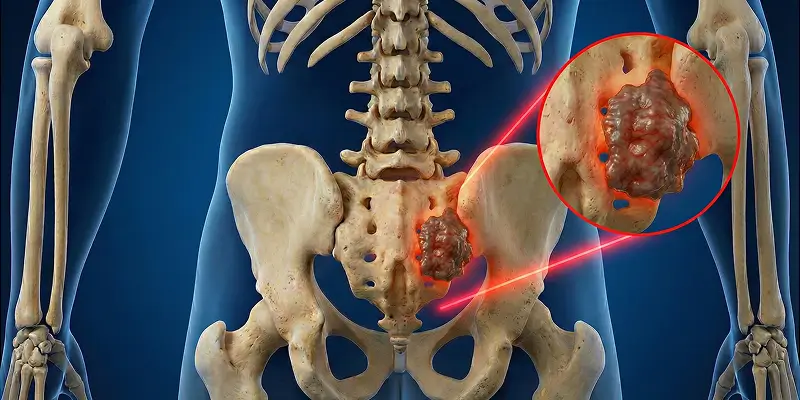

Kemik metastazı, başka organlardan kemiğe yayılan kanserin neden olduğu ciddi bir durumdur. Belirtileri, teşhisi, tedavi yöntemleri ve ağrı yönetimi.

Dev hücreli kemik tümörü, osteoklastik dev hücrelerin kontrolsüz çoğalmasıyla oluşan agresif bir kemik tümörüdür. Belirtileri, tanı yöntemleri ve tedavi seçenekleri.

Başka organdan kemiğe sıçrayan kanserlerde (metastaz) kırık riskini önleyen cerrahiler ve ağrı yönetimi. Ortopedik onkolojide metastaz yaklaşımı.